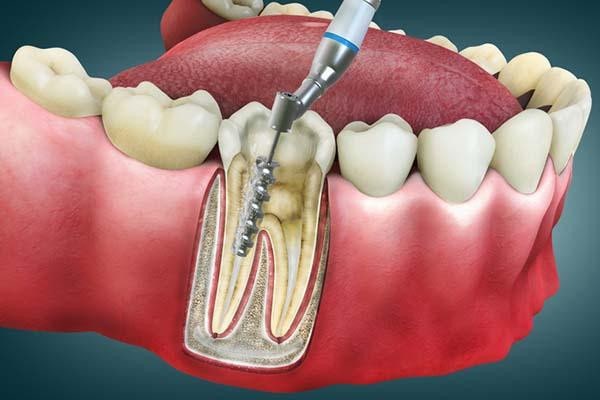

تعداد کانال های دندان از عوامل مهم در تعیین هزینه عصب کشی دندان است. بهتر است بدانید معمولا دندان ها یک کاناله، دو کاناله یا سه کاناله هستند. هر چه تعداد کانال ها بیشتر باشد، درمان زمان برتر و پیچیده تر خواهد بود و در نتیجه هزینه نهایی افزایش می یابد. منظور از کانال، پالپ های شامل عصب ها و رگ های خونی هستند که در داخل مجراهایی قرار دارد که به آن کانال دندان گفته می شود.